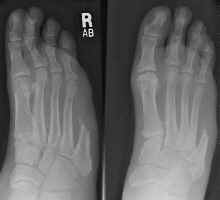

Boarder ray amputations do not significantly interfere with

ambulation. In fact, amputation of the lateral two or even three rays often provides

a functional weight-bearing foot. Amputation of the medial two and even three rays

in special circumstances may provide a weight-bearing, sensitive, reasonably functional

foot (See below).